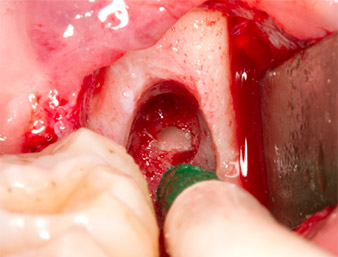

Sous bloc nerveux et anesthésie locale, le site d’intervention est ouvert et les tissus mous sont exposés afin d’accéder à la zone rétromolaire buccale (Fig. 3).

Le tissu recouvrant le reste radiculaire n’est pas entièrement ossifié et est essentiellement constitué de tissu de granulation modifié par l'inflammation (Fig. 4).